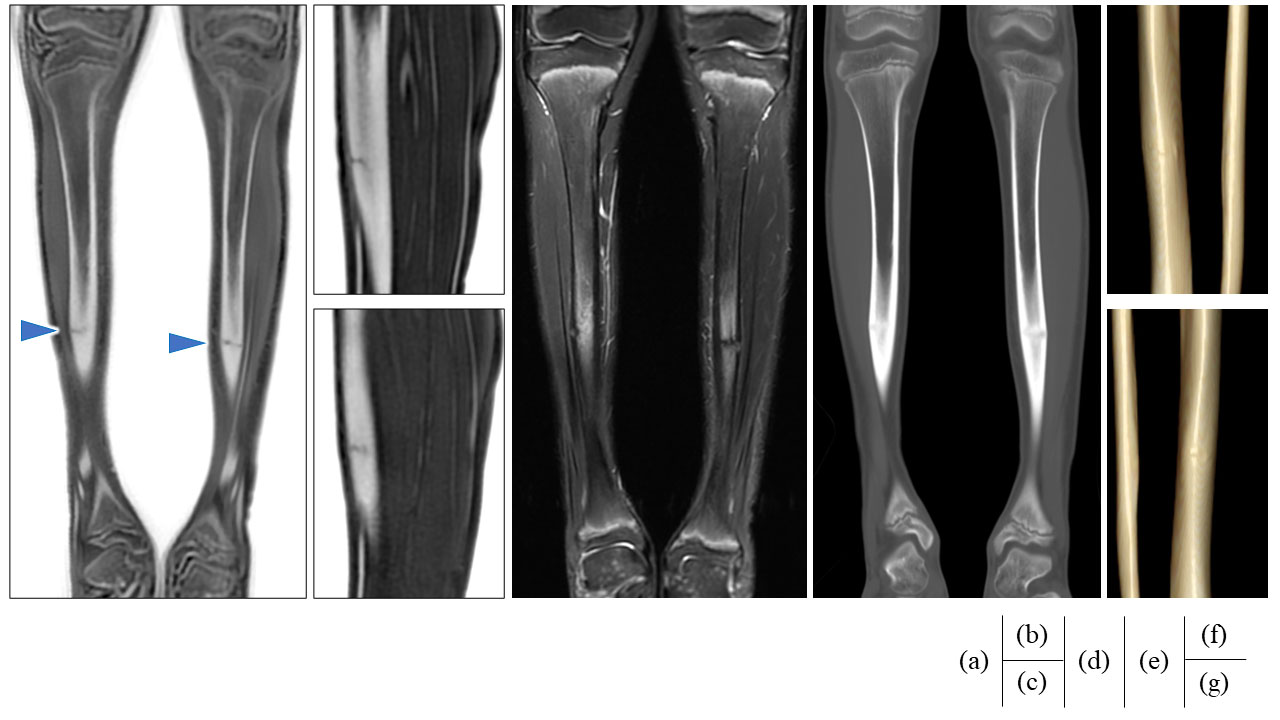

Fig.8はCTで確定診断に至らなかった疲労骨折をoZTEoにて明瞭に描出した一例である. (e)はCT骨条件であるが骨折線がはっきりしない上, 骨肥厚が左右対称であるため骨折とは診断されなかった. (f)(g)のCT VR像でも骨折線は確認されない. (a)(b)(c)はoZTEoであるが, 骨皮質のみが高信号となるため, 左右非対称な骨折線が一目瞭然である. (d) STIRにおいても, 骨折線周囲の炎症が確認され, 疲労骨折との確定診断に至った.

Artist_Yokohamaminamikyousai11.jpgFig.8 CTで確定診断に至らなかった疲労骨折をoZTEoで明瞭に描出した一例

(a) oZTEo Coronal (原画像), (b) L-Leg Sag (Reformat), (c) R-Leg Sag (reformat),

(d) STIR Coronal, (e) CT 骨条件 (Reformat), (f) CT VR画像 L-Leg, (g) CT VR画像 R-Leg